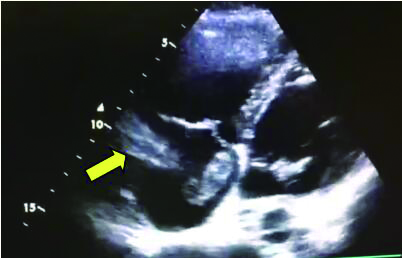

1 经典的挽救性溶栓治疗策略可能带给医生更多的是被动和难度例1 男性,28岁,体质量90 kg。主诉“胸闷、憋气1周加重1 d”。既往:体健;喜久坐(平均10~15 h/d);否认手术史、外伤史;入院查体:神志清楚,体温36.8℃,血压128/80 mmHg(1 mmHg=0.133 kPa),脉搏120次/min,呼吸26次/min,脉氧饱和度96%(安静,空气氧),未见明显乏氧征。双肺呼吸音清,未闻及干湿性啰音。心率120次/min,心律齐,P2 > A2,心界无扩大,无杂音。腹软,无压痛,肠鸣音正常,双下肢无浮肿。神经系统查体未见异常。血气分析(空气氧)提示pH 7.514,PaCO2 27.2 mmHg,PaO2 67.1 mmHg,SaO2 95.0%;D-Dimer:3 035 ng/mL,FDP 33.08 μg/mL,FBG 4.520 g/L;PLT 179.0 G/L,TNI 0.08 ng/mL,BNP 882.00 pg/mL;ALT 38 U/L,AST 17 U/L,CREA 82.6 μmol/L,血Na+、K+、Cl-正常范围;超声心动图(Ultrasonic Cardiogram,UCG)提示:右心增大,肺动脉主干及右肺动脉增宽,肺动脉主干32 mm,三尖瓣反流(重度),反流面积8.6 cm2,TI法估计SPAP为67 mmHg、左室舒末内径50 mm、左室E/A:45/38 cm/s, 左室壁厚度及运动正常,未见节段性室壁运动障碍;双下肢静脉超声提示左侧股静脉血栓形成可能(完全型)。心电图(图 1所示)提示窦性心动过速;肺动脉增强CT(Computed tomographic pulmonary angiography, CTPA)提示双肺主干明确充盈缺损(图 2所示)。入院诊断:急性肺血栓栓塞症(中高危)。入院后给予抗凝治疗(依诺肝素钠90 mg,皮下注射,1次/12 h)重叠华法令治疗的第4天D-Dimer升至47 482 ng/mL,第6天2 411 ng/mL。第7天常规复查双下肢超声未见新增血栓形成,复查UCG(当天INR 2.25)提示右心房漂浮血栓,并随心脏蠕动明显(图 3所示)。在准备胸外科手术取栓的过程中出现血压下降至70/40 mmHg,脉氧饱和度降至45%,立即给予气管插管并系统溶栓治疗(r-tPA 100 mg于2 h输注),溶栓治疗1.5 h患者血压逐渐回升并趋于稳定、溶栓治疗3 h自主呼吸开始恢复,于插管3天后(住院第10天)拔出气管插管,成功撤离呼吸机。溶栓过程中曾经出现消化道、气道出血,血红蛋白下降1.9 g/dL,未予输血治疗。溶栓后复查CTPA提示双肺主干血栓负荷明显减少,远段血液灌注明显增加(图 4所示)。

| 图 3 入院1周复查超声心动提示右心房漂浮血栓(黄色箭头) |